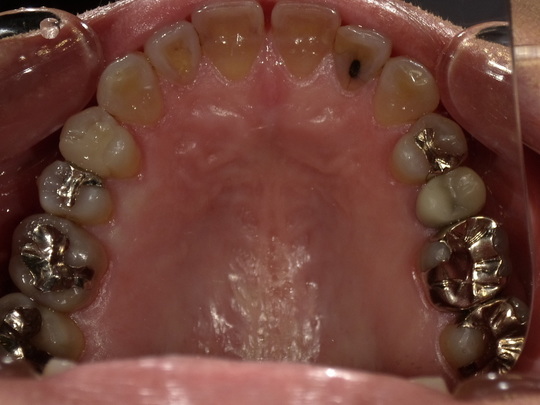

年齢:70代女性

治療内容:奥歯の銀歯が気になるという主訴で、右上中央から3,4,5番目をe.maxにより修復

治療期間/通院回数:3回

費用: e.max クラウン 110,000円x3本 ※2025年7月現在の価格